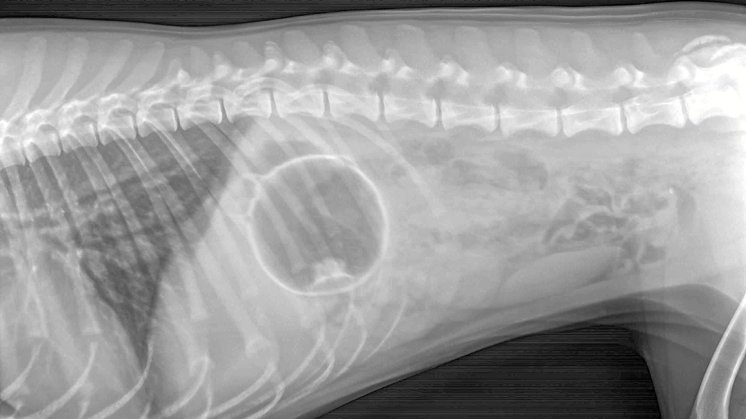

Her kan man se hele omridset af en gummibold, der ligger i mavesækken Foto: Johannes Fogh

Her kan man se hele omridset af en gummibold, der ligger i mavesækken Foto: Johannes Fogh Johannes Fogh